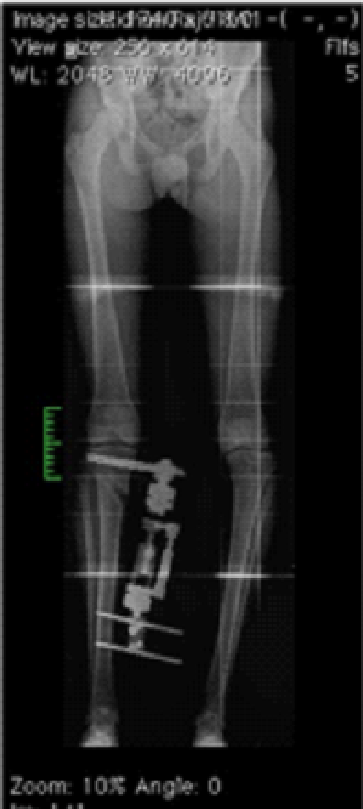

Dr.Jijeesh Dr.Jijeesh HTO is a surgical procedure used to correct the Tibial varus deformity. It is done in genu varus or bowleg. Bowleg is a condition in which the legs have a gradual or sudden bent due to various reasons. The term varus means bent inwards and the term valgus means bent outward Normally, on standing both the knees bear equal weight. And in the knee the weight distribution is more on medial or inner side than outer side. So any increase in small degree of varus will cause more force on the medial side than lateral side. In case of valgus small degree wont have much effect on the lateral side. When a person has bowlegs there is increased load on the inner side of the knee more commonly (Varus) or the outer side of the knee (Valgus). This increased loading causes that side to wear out faster and then presents as pain. Generally the body is able to compensate slight bow in the legs by the action of muscles. But when the bent is beyond a certain limit then the muscles cannot compensate and this results in reduction in the joint space and gradual worsening of the angle. When the cartilage of the joint wears out it is called reduced joint space or arthritis knee, which is due to overload. These arthritic changes are called secondary osteoarthritis Ie, arthritis due to bend or some secondary cause. Whereas primary osteoarthritis is the term used in case of wear and tear of knee joint due to old So, in these type of arthritis ie arthritis due to varus otherwise known as medial compartment osteoarthritis the treatment is to correct the alignment of the knee by doing a surgery called High Tibial Osteotomy. HTO is indicated not in all patients with genu Varus. Occasional pain that settles with rest doesn’t require surgery immediately. Generally, in about 80-90% people this settles down with proper exercises and medication for a few days. But if there is worsening on the x-rays even without much pain, then there is a role of correction of the deformity as a “preventive surgery”.

By changing the angle of bone the bow is corrected and the load-bearing axis or the mechanical axis of the limb is brought back to the center of the knee joint. This shift helps in taking the load off the affected side and relieves the pain, but more importantly it helps the overloaded side to get rest and heal. As the healing progresses the narrowed joint space again fills up cartilage. In HTO the principle is to cut the Tibia through a small incision (about 1.5 cm) few inches below the knee; an external fixator is applied to the bone; the angle is then gradually corrected by turning a nut on the fixator (1 mm per day) to a pre-defined point and the fixator is then locked. The fixator remains for a total of 3 months, because that is the time for the bone to heal and become solid. Once the bone healed the Fixator can be removed as an OPD procedure. And there is no. need of any second surgery. The second method is HTO using plate. Here instead of orhofix fixator plate is used for fixation of bone. The advantage is, there is no implant outside the body. But the disadvantage is to get a perfect alignment on standing weight bearing in all cases.